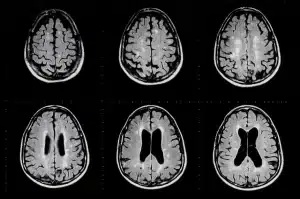

Epilepsy is a neurological disorder characterized by recurrent seizures. Learn what epilepsy is, what seizures are, and why we need a cure.

Epilepsy is a diverse group of neurological disorders which are characterized by recurrent seizures. Learn what causes seizures and how they’re classified.